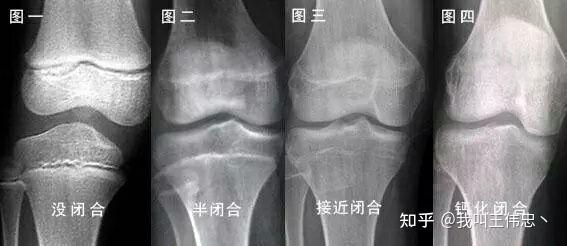

不知道你说的成年是否指18岁以后。身高增长的原理是骺软骨增殖,而骺软骨会在18-25岁之间发生骨化,此时身高也就停止增长了。

要想确定骺软骨是否发生骨化,建议去正规医院拍个手部和腕部的骨龄片。